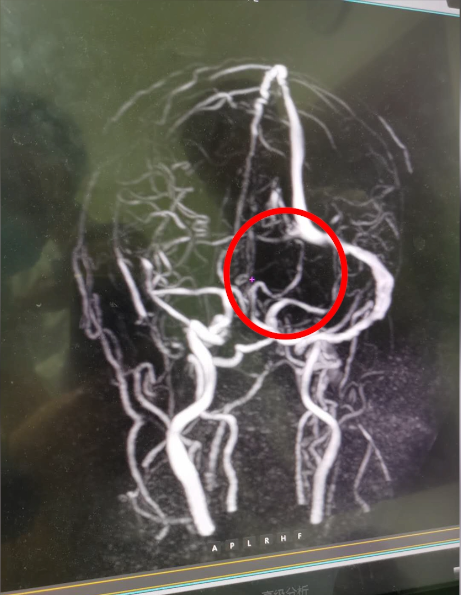

头颅MRV检查发现血栓形成

该病在临床上并不多见,因此容易漏诊和误诊。患者经常被误诊为脑动脉性梗死、脑肿瘤、脑部感染等。CT核磁共振可看到间接征象,但直接征象主要依靠MR静脉成像(MRV)。